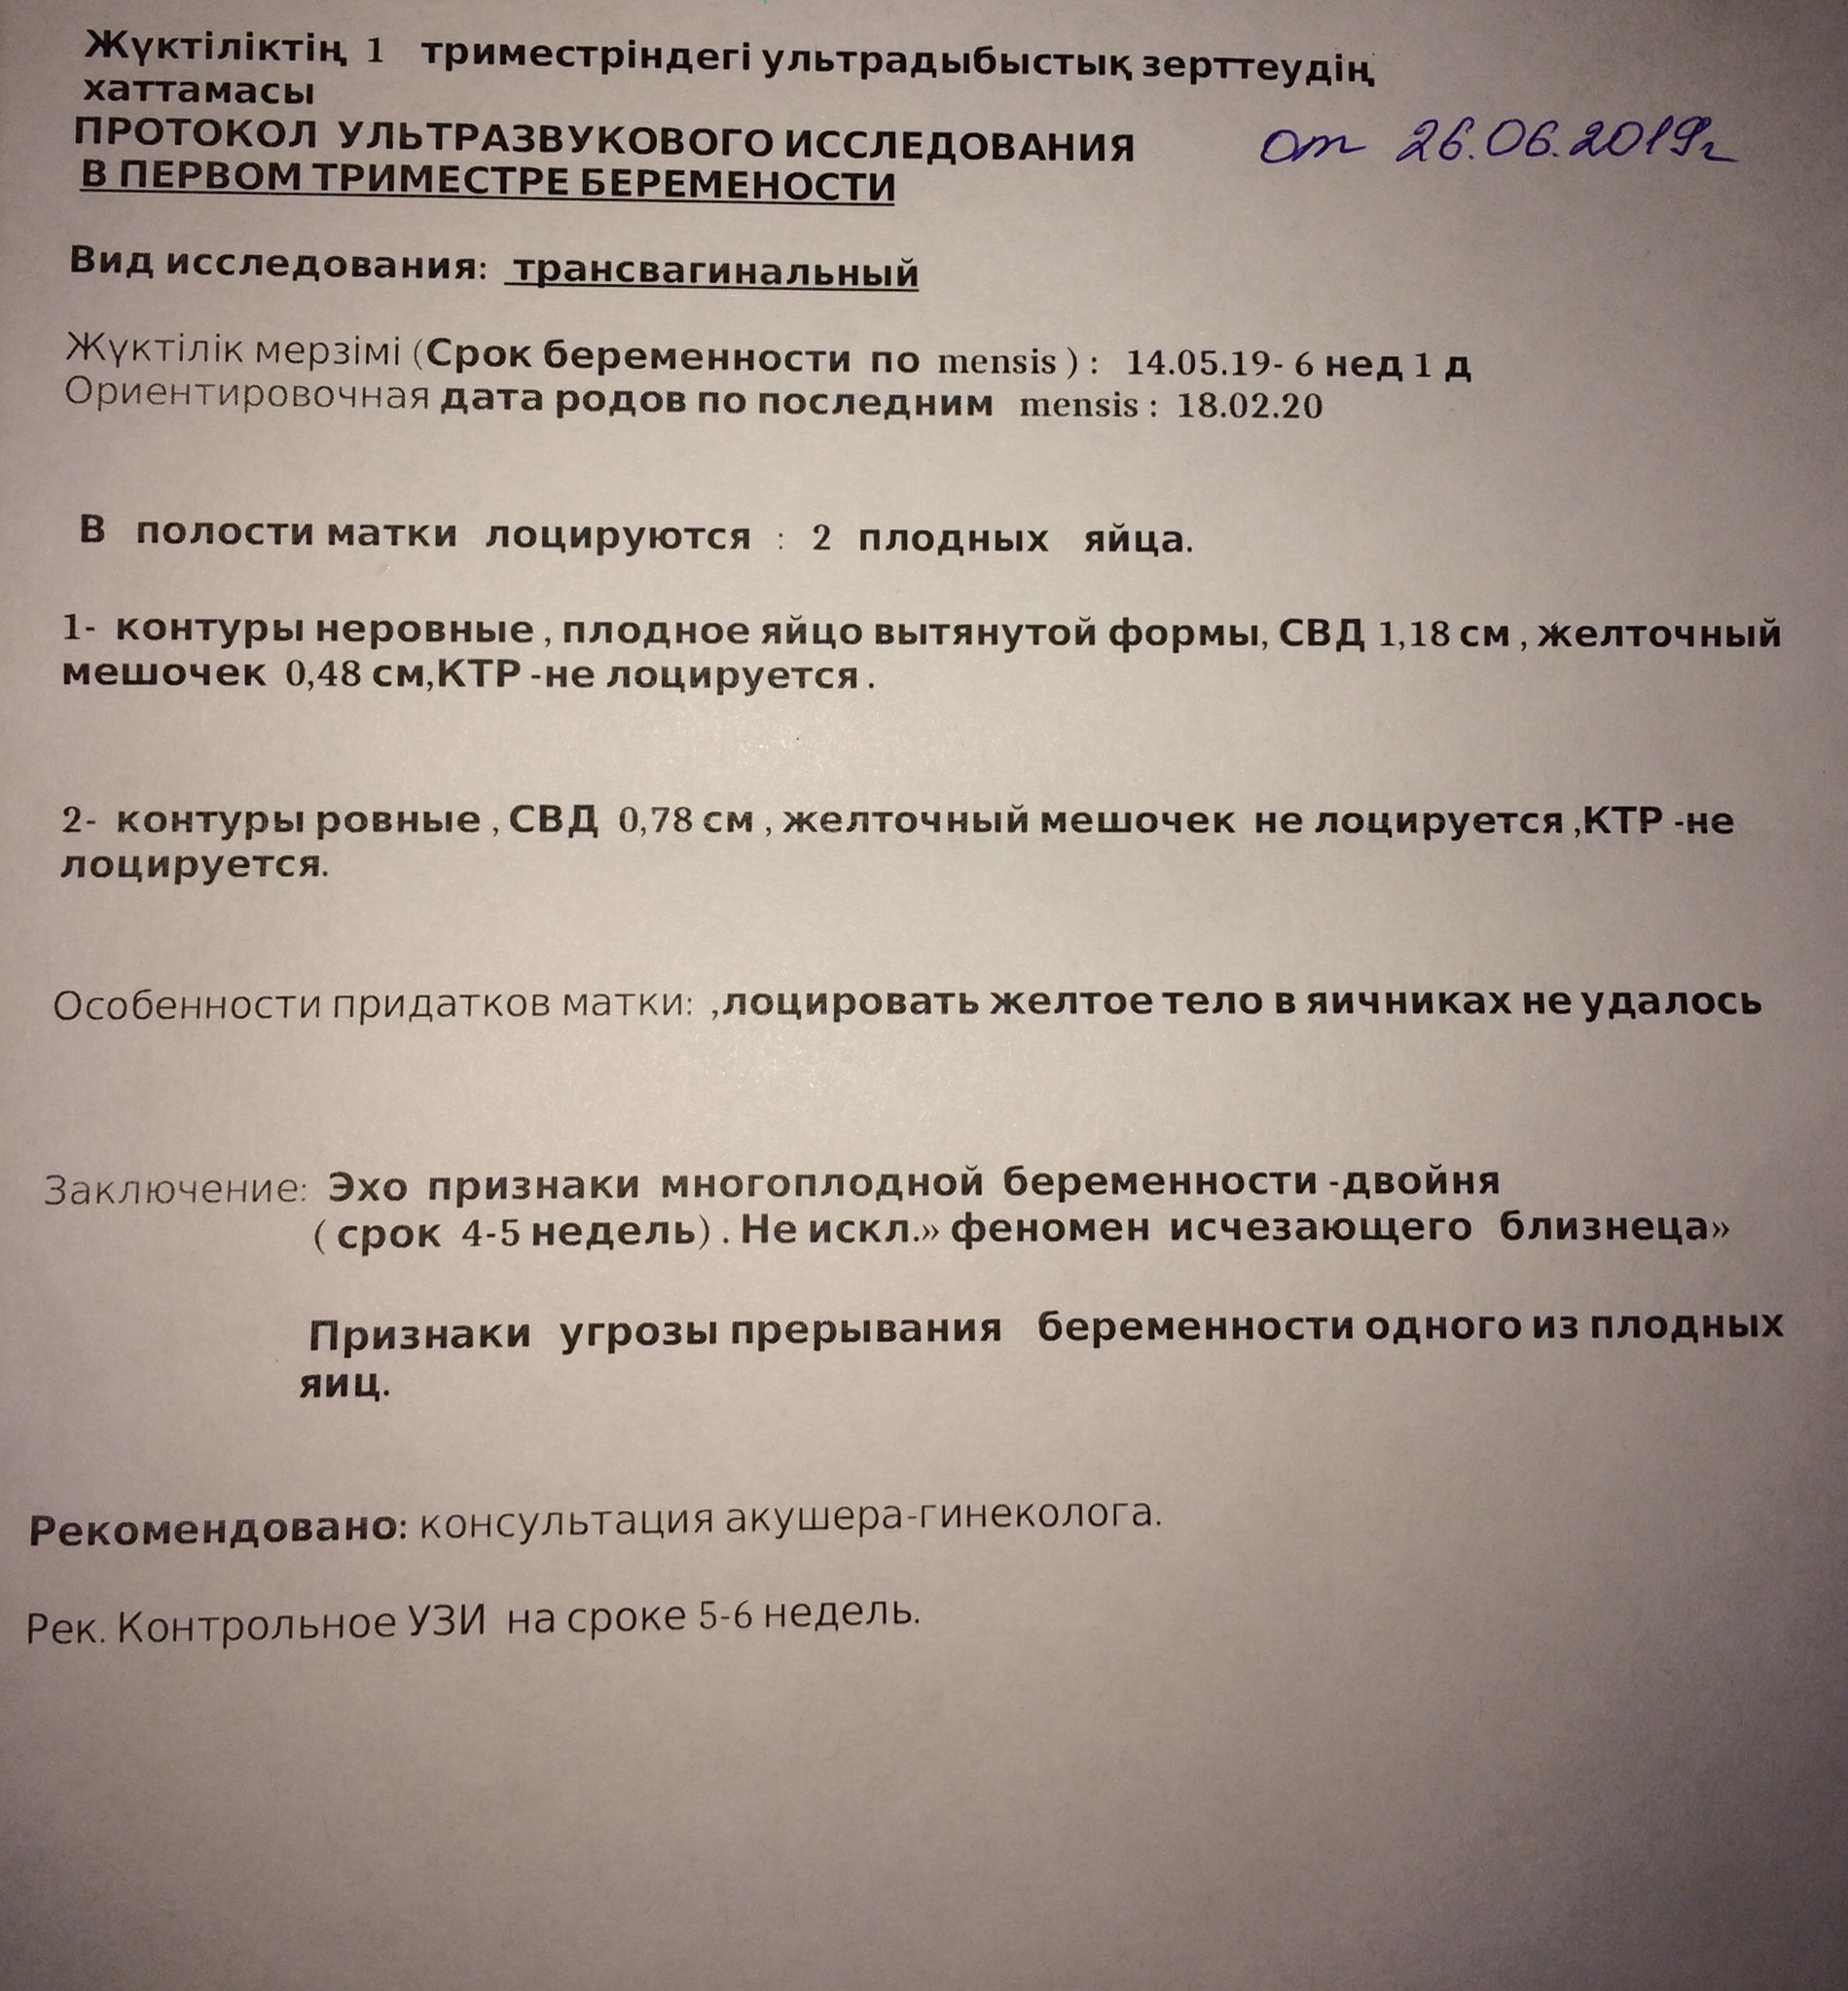

УЗИ двухплодной беременности на 5 неделе: Подборка изображений

Раздел: Калейдоскоп образов